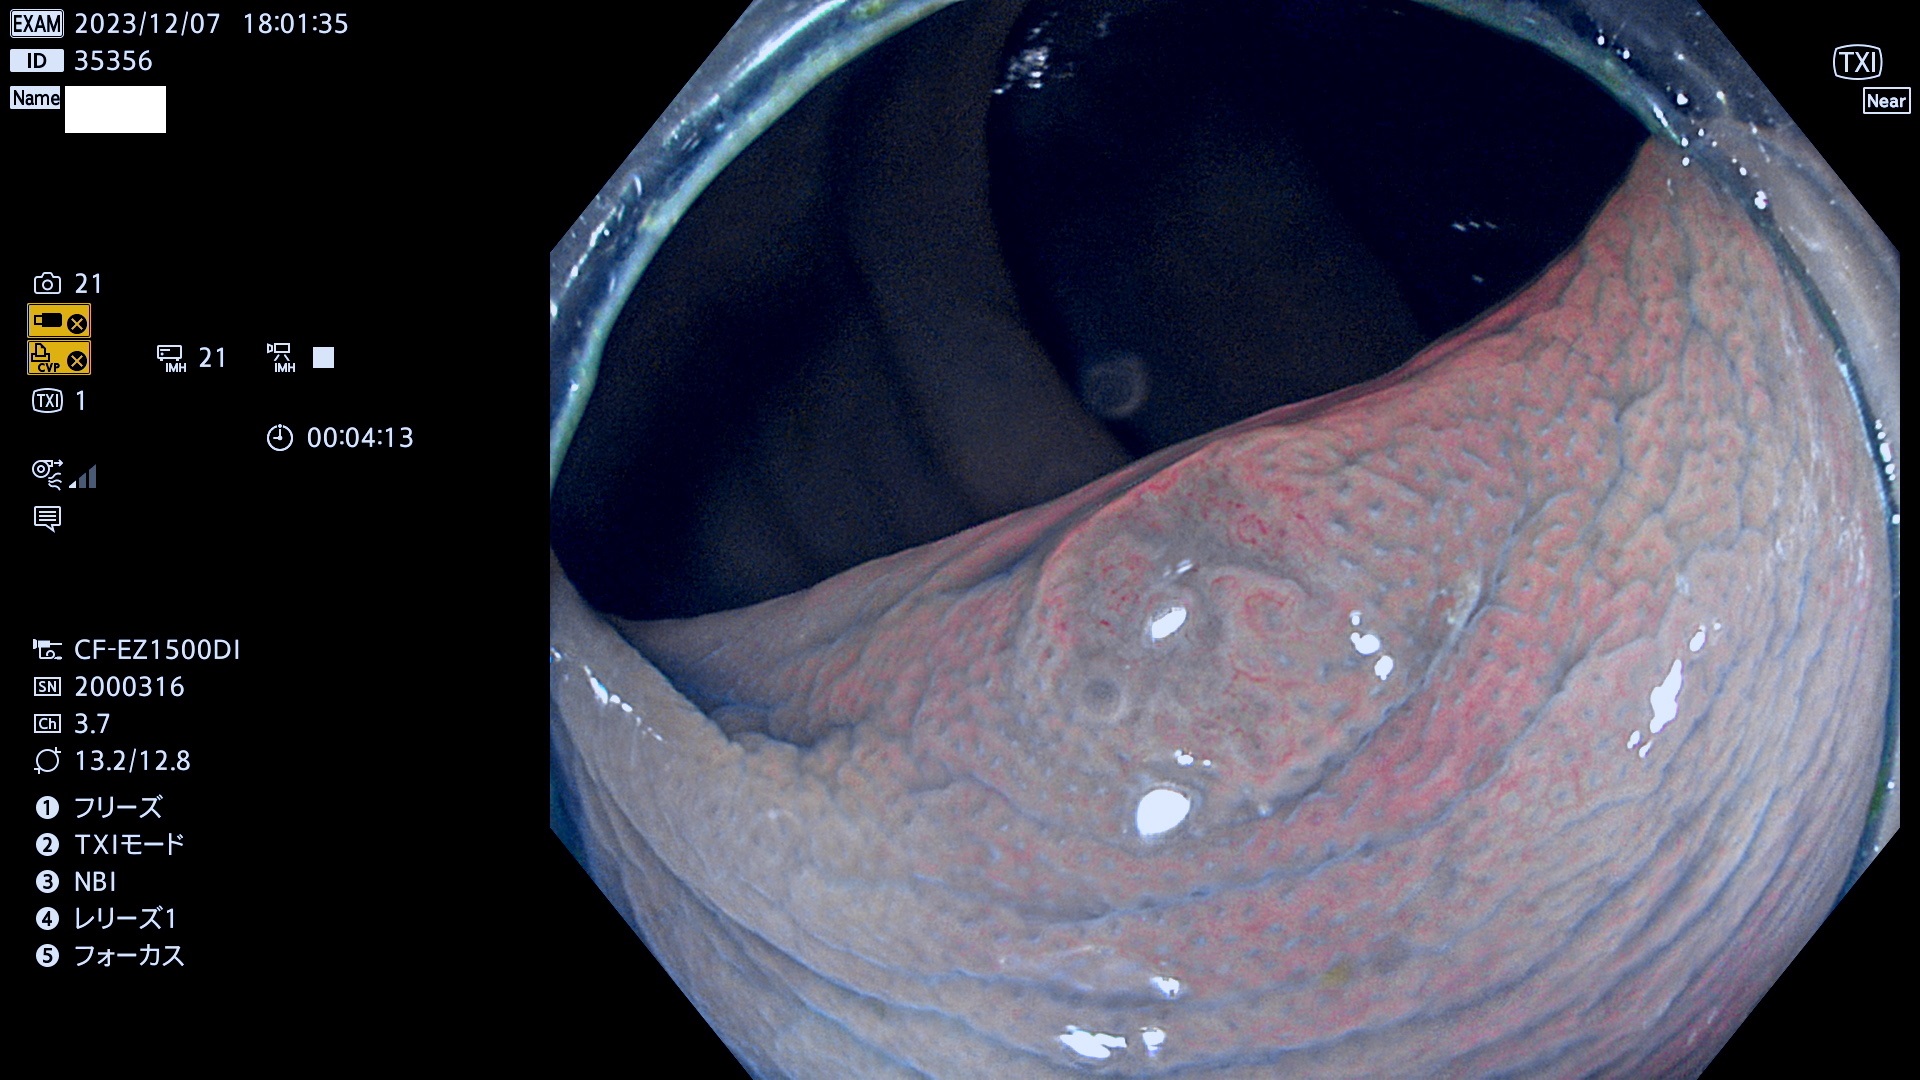

今週のUb、Uc型腺腫

表面型腺腫(Flat Adenoma)の中で、完全に平坦な物をUb、陥凹している物をUcと呼びます。平坦隆起型(Ua)よりも、発見が難しく危険な病変です。このタイプは「内視鏡後・大腸癌の重要犯人」であり、この発見率は「腺腫発見率」よりも、重要な意味があります。

毎週の検査(木・金・土・日)に発見されたUb、Uc型・腺腫を、その週の日曜の夜にUPし1週間、提示します。

抽出の対象期間 2023年12月7日(木)〜12月10(日)の4日間(48件の検査)12件